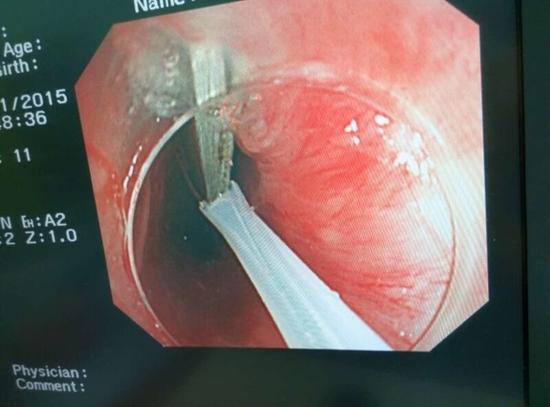

醫生從華先生胃里取出的鑷子和打火機

隨后,范醫生先用圈套器套取出了長10厘米的鑷子,再一個一個地取出了打火機。整個取出過程小心謹慎而又一氣呵成,只用了不到10分鐘。